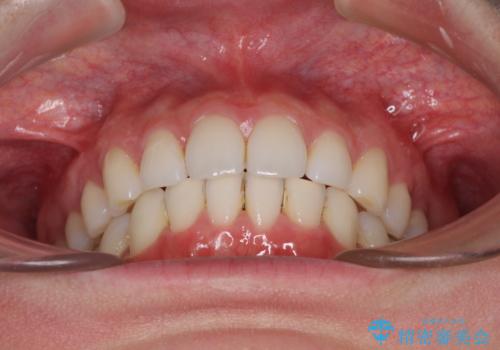

- 上下前歯の叢生を気にして来院された患者様です。

以前矯正をした後戻りということで、歯列不正はそれほど大きくなかったため、インビザライン・ライトを用いて矯正治療を行うこととしました。

前歯のデコボコが残っており、シミュレーション通りに動いていない部分がありましたが、再矯正であることやご本人の満足いくところまでデコボコが改善されたとのことで、治療を終了することとしました。